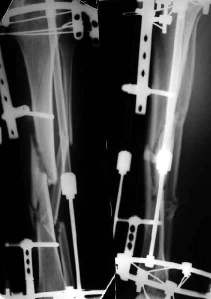

У нас, наверно, была бы сделана чрескожная остеотомия малоберцовой кости, формирование и рассверливание канала большеберцовой, закрытая остеоклазия, и закрытое же штифтование. За счет устранения варуса дефицит длины уменьшится. Можно и подтянуть дистрактором одномоментно.

При невозможности или чрезмерной травматичности одномоментного восстановления длины можно пойти двухэтапно (аппарат, потом гвоздь). Похожий пример см. тут. Прошло уже года полтора после остеосинтеза. Может, коллега Зырянов покажет годичный результат, если есть?

Александр Николаевич, к сожалению больной не является на контрольные осмотры. Я последний раз видел больного, когда прошло 7 месяцев после операции БОС. У него все хорошо. Каких либо жалоб и ограничений в нагрузке нет. Высылаю снимки до операции и последние снимки.